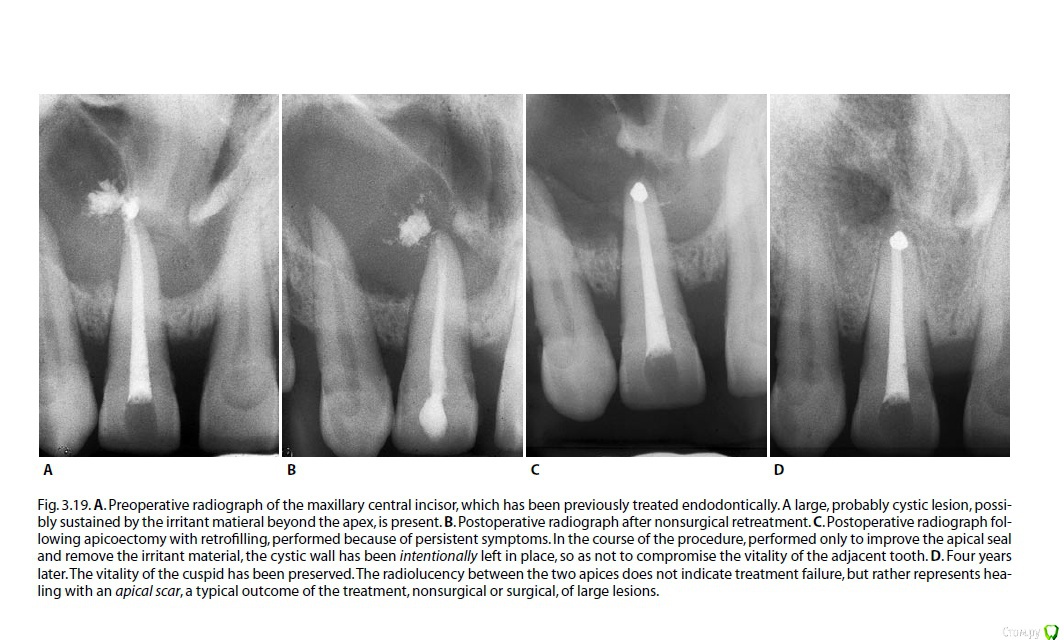

Fred Опубликовано 2 марта, 2017 Поделиться Опубликовано 2 марта, 2017 Я до сих пор толком не разбираюсь в "кистологии". Давайте и на этом форуме побеседуем. Теоретический вопрос - исчезнет ли киста в 100% случаев, если СКК стерилизировать и стерильность ее поддерживать на продолжительном отрезке времени? "Давайте обновим знания в "кистологии".Обратилась ко мне пациента по почте с кистоподобным образованием в области верхней челюсти, у передних зубов (прилагаю ее снимки в первой картинке: первый снимок - полгода назад, другие - на днях). Недавняя моя неудача с много раз презентированным на форумах случаях с кистообразным поражением заставило меня посидеть с литературой и еще раз понять, что же такое происходит во время таких поражений, и что мешает возникнуть заживлению Пациентка утверждала, что канал ей пломбировали года 3 назад, но теперь снова возникла симптоматика и опухание. Рядомстоящие витальные, но резец уже депульпировали, так как собираются кисту вырезать.Я еще раз хочу разобраться, если киста стерильна, то почему возникает симптоматика? Может симптоматику в таких случаях поддерживает то, что мы не можем идеально запломбировать канал, и несмотря на красивую рнг-картинку, мы имеем некачественную обтурацию в апексе, которая и поддерживает временно обостряющуюся клинику? Может образованию не дает возможность исчезнуть то, что это пузырь с жидкостью, хоть и стерильный, и в нем не могут возникнуть репарационные процессы, так как в нем нет кровотока? Может нужно все-таки его насильно сдувать, сплющивать, вырезать? Вчера прочитал раздел Кастеллучи про периапикальные поражения (обновил знания, давно за стоматологическими книгами не сидел), и понял, что все это лечится либо банальной эндодонтией, либо ретроградкой, если эндо не получилось. Никаких специальных хирургических методов, никаких вырезаний, никаких жертв витальности соседних зубов.Так нужен ли специальный подход к "кистам"?Побеседуем?Кто захочет тоже почитать Кастеллучи, но не имеет, просите, дам ссылку или перешлю." 3 Ссылка на комментарий

Fred Опубликовано 2 марта, 2017 Автор Поделиться Опубликовано 2 марта, 2017 Не значит ли это, что неудача при эндолечении кисты только потому, что не получилось вычистить и обтурировать канал (сложности анатомии, инфицированные дентинные тубулы, блок системы каналов). Иначе говоря, вылущивание кисты - дело бессмысленное?И что такое "истинная киста"? Ссылка на комментарий

Ico Опубликовано 2 марта, 2017 Поделиться Опубликовано 2 марта, 2017 Не значит ли это, что неудача при эндолечении кисты только потому, что не получилось вычистить и обтурировать канал (сложности анатомии, инфицированные дентинные тубулы, блок системы каналов). Иначе говоря, вылущивание кисты - дело бессмысленное?И что такое "истинная киста"?Я считаю,что не получится полностью стерилизовать канал хоть как ты его мой.А вот сократитив некую "критическую массу" микробов можно получить хилинг,и чем лучше почистили тем быстрее заживление.Полный "хилед" можно оценить лет черз 5 только к.м.к))).По части вылущивания кисты,тут спорно,хотя есть показания но они размытые.Например оверфилинг и резорбция с раздолбанным апексом. Ссылка на комментарий

Л Ю С Я Опубликовано 2 марта, 2017 Поделиться Опубликовано 2 марта, 2017 Думаю не только дело в дезинфекции и обтурации апекса. Хотя это основное. Видимо в некоторых случаях киста продолжает жить своей жизнью и пока не выскоблишь оболочку не уйдёт Ссылка на комментарий